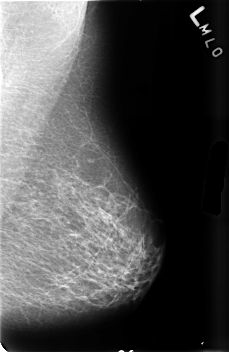

B_3458_1.LEFT_MLO

LEFT_MLO LINES 4576 PIXELS_PER_LINE 2976 BITS_PER_PIXEL 12 RESOLUTION 50 NON_OVERLAY